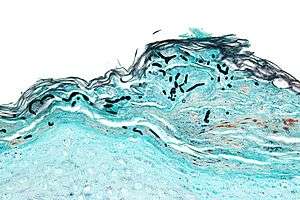

| Micrograph of a superficial dermatomycosis. The fungal organisms are the dark staining, thick, quasi-linear objects below with skin surface. Vulvar biopsy. GMS stain. | |